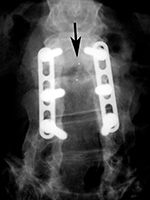

Posterior spinal fusion apparatus |

Shown are pedicle screws and rods on each side, two crosslinks (at L4 and S1), and intervertebral disk spacers at L4-5. |